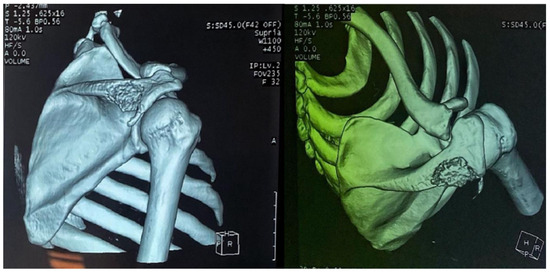

Figure 5. A 3D reconstruction of the right shoulder joint, showing the lytic lesion of the scapular spine.

Computed tomography of the right shoulder showed a lytic lesion of the right scapula with cortical rupture associated with scapular osteomyelitis (Figure 3, Figure 4 and Figure 5). The lesion was complicated by a deltoid abscess measuring 75 × 29 mm and extending over 105 mm (Figure 4), without joint effusion.

Clinically, osteoarticular TB can mimic other inflammatory and neoplastic bone lesions such as pyogenic osteomyelitis, fungal infection, multiple myeloma and metastatic disease [8]. For our case, the presence of any other germ was ruled out by pus culture and even multiplex PCR. The radiological features of skeletal TB are not specific. They may vary from lytic lesions and periarticular osteoporosis to bone marrow oedema, joint effusion, tenosynovitis and soft tissue collections [9], as in our patient, in whom a CT scan of the shoulder revealed bone lysis of the ½ distal scapular spine with cortical rupture and deltoid collection.